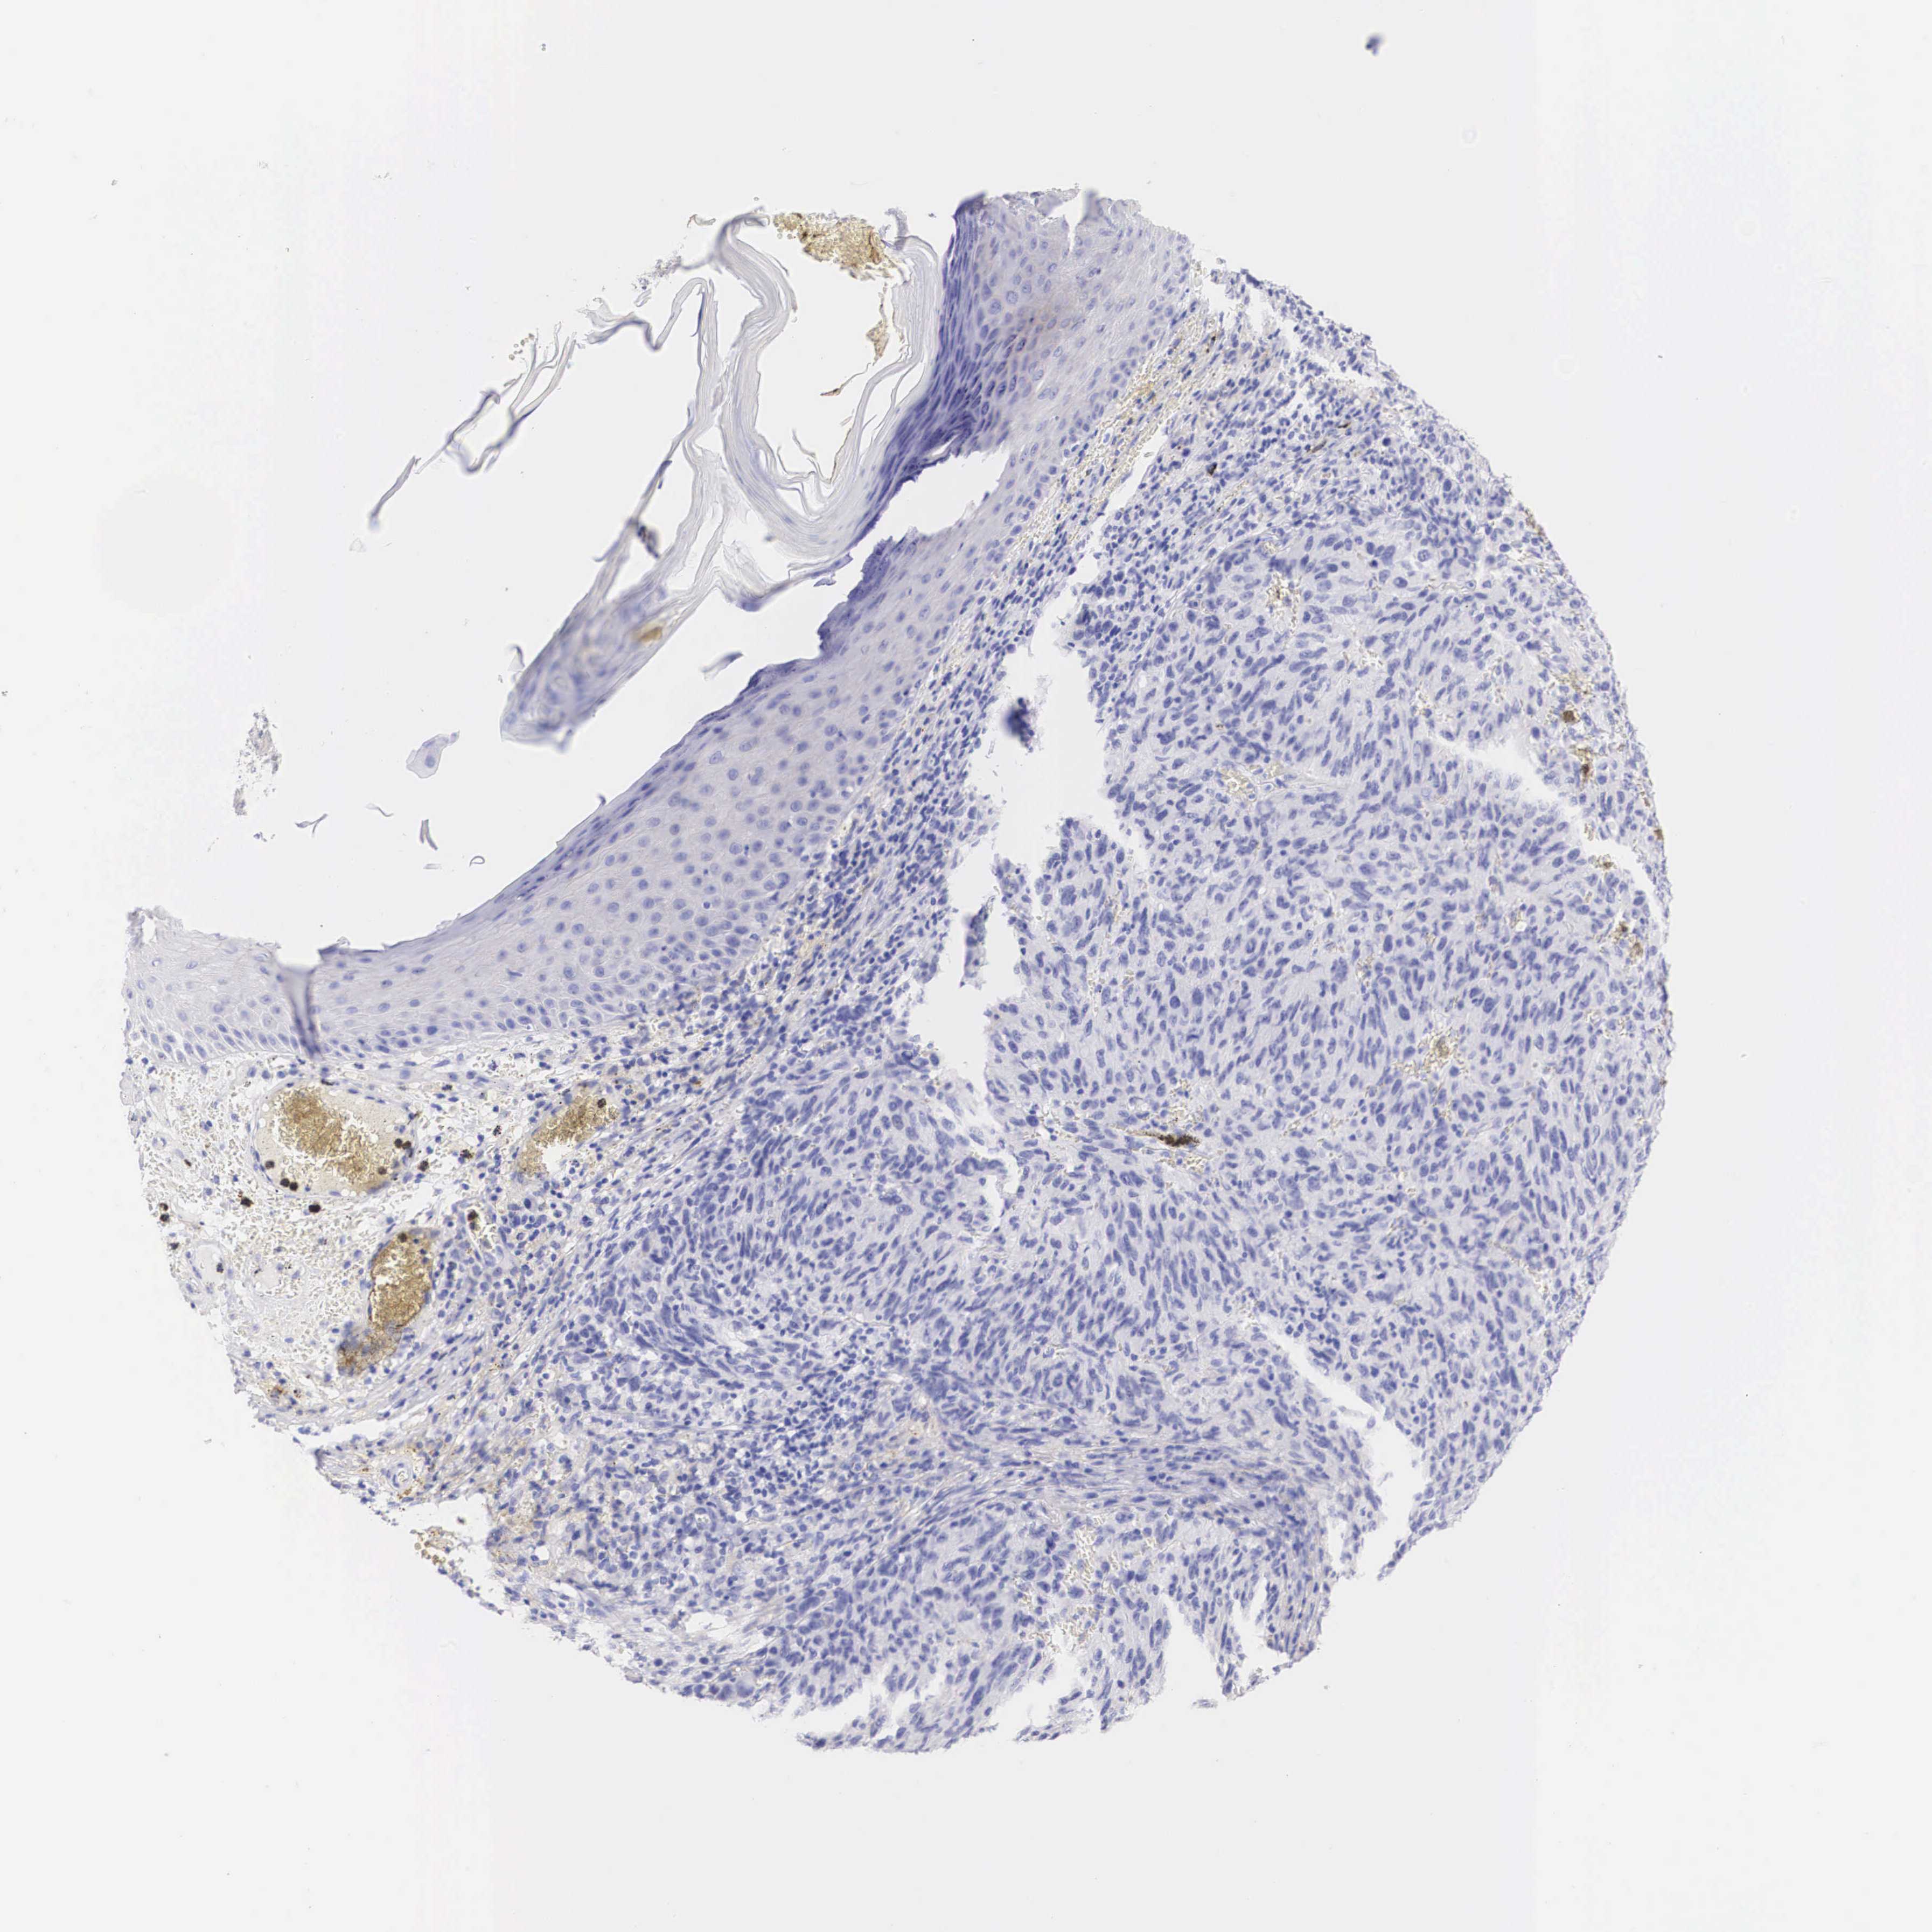

MELANOMA - Protein expressioni

A mouse-over function shows sample information and annotation data. Click on an image to view it in a full screen mode. Samples can be filtered based on level of antibody staining by selecting one or several of the following categories: high, medium, low and not detected. The assay and annotation is described here.

Note that samples used for immunohistochemistry by the Human Protein Atlas do not correspond to samples in the TCGA dataset.

Antibody stainingi

Antibody staining in the annotated cell types in the current human tissue is reported as not detected, low, medium, or high, based on conventional immunohistochemistry profiling in selected tissues. This score is based on the combination of the staining intensity and fraction of stained cells.

Each image is clickable and will lead to virtual microscopy that enables deeper exploration of all samples and also displays staining intensity scores, fraction scores and subcellular localization as well as patient and tissue information for each sample.

Malignant melanoma, NOS

Malignant melanoma, Metastatic site